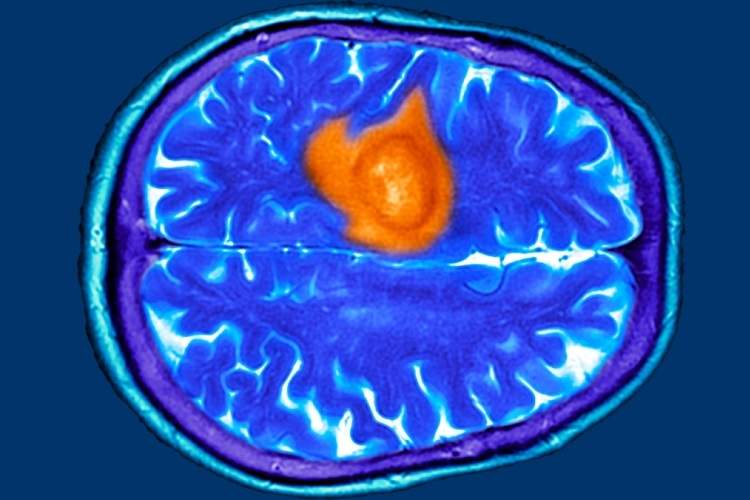

هفت نشانه پنهان تومور مغزی که ممکن است آنها را عادی بپندارید

به گزارش اخبار زنده و به نقل از ساینسآلرت، پژوهشهای اخیر نشان میدهد که بیماران و پزشکان عمومی در مراحل اولیه اغلب این نشانهها را نادیده میگیرند و همین امر باعث تأخیر در تشخیص میشود. از آنجا که درمان تومور مغزی در مراحل پیشرفته دشوارتر است، شناسایی علائم اولیه اهمیت ویژهای دارد.

تومور مغزی میتواند با علائمی مشابه بیماریهای رایج مانند اضطراب، عفونت سینوس یا یائسگی بروز کند. در پژوهشی که بر پایه مصاحبه با بیماران انجام شد، هفت علامت اصلی شایع اما فریبنده شناسایی شد. نخستین مورد، دشواری در یافتن کلمات است؛ برخی بیماران در صحبت کردن یا کامل کردن جمله دچار وقفه میشدند، موضوعی که ابتدا به استرس یا خستگی نسبت داده شد. دوم، مهذهنی یا Brain Fog است که با ناتوانی در تمرکز و فراموشی همراه میشود. اگر این حالت با مشکلات گفتاری یا بینایی همراه شود، نیاز به بررسی پزشکی دارد.